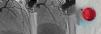

Isolated left ventricular noncompaction (LVNC) is a form of cardiomyopathy resulting from persistence of fetal trabeculations and intertrabecular recesses within ventricular myocardium. The clinical features associated with LVNC consist of left ventricular (LV) systolic dysfunction, arrhythmias, and thromboembolic events. We report the case of a 67-year-old woman admitted to the emergency department with acute aphasia, dyspnea, and peripheral edema associated with recent-onset paroxysmal atrial fibrillation (AF) with high ventricular rate. After anticoagulation with unfractionated heparin (UFH), she was converted to stable sinus rhythm with intravenous (IV) amiodarone. She was then admitted to the intensive coronary care unit (ICCU) and treated with IV inotropes and diuretics, resulting in prompt recovery from aphasia and improvement in congestion. The echocardiogram showed a markedly dilated left ventricle with hypertrabeculation of the apex and of the inferior-inferolateral segments (noncompacted/compacted ratio 2:1), severely reduced ejection fraction (EF) (22%), and an apical thrombus. No significant carotid artery disease was found on Doppler echocardiography. She underwent implantation of an implantable cardioverter-defibrillator and was discharged in NYHA class II, under standard heart failure therapy including oral anticoagulation (OAC), with no evidence of thrombosis (Figure 1). Twelve months later, due to a major depressive episode, the patient failed to attend the scheduled heart failure clinic (HFC) follow-up and discontinued OAC. Due to recurrent dyspnea and fatigue she presented to the HFC, where an echocardiogram showed a massive LV thrombosis (Figure 2), so she was admitted to the ICCU and IV UFH was started. After two days the patient complained of chest pain; as the ECG showed marked ST segment elevation in V3-V6 she was referred to the catheterization lab. Coronary angiography revealed a thrombotic occlusion of the mid segment of the left anterior descending artery (Figure 3A); the clot was aspirated and no significant coronary artery disease (CAD) was found (Figure 3B and C). A marked increase in plasma troponin I was observed, confirming the diagnosis of acute embolic myocardial infarction (MI). Her EF fell to 15% and after two days she became hypotensive despite intra-aortic balloon pump and inotropic support, with cardiogenic shock and acute kidney failure. She was considered for a left ventricular assist device, but sepsis and multiorgan failure occurred, and death followed 25 days later.

(A) Left coronary angiogram showing a thrombotic total occlusion in the mid segment of the left anterior descending artery (LAD); (B) left coronary angiogram following percutaneous coronary intervention showing no significant stenoses; (C) thrombotic material retrieved from the LAD by thrombus aspiration.